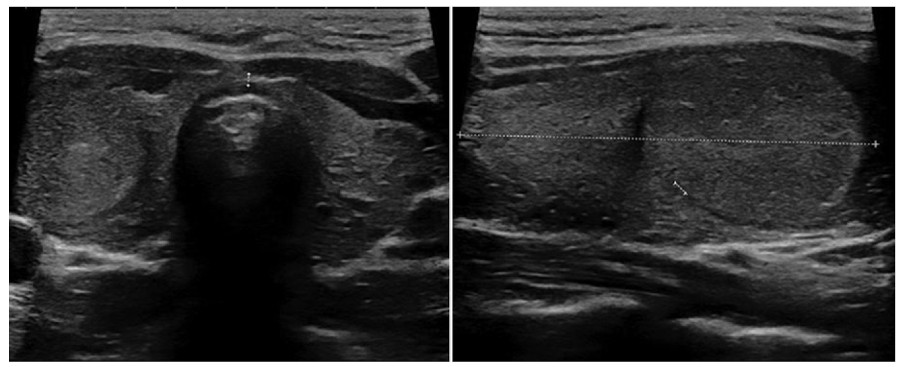

Márgenes

Es el borde entre el nódulo y el parénquima tiroideo adyacente o las estructuras extratiroideas. Se clasifican en “lisos” (Fig. 4) cuando son bien definidos, curvilíneos, de forma esférica o elíptica y no presentan interrupción en su extensión; “irregulares” (Fig. 5) cuando son espiculados o dentados, y puede dibujarse todo el contorno, lo que los diferencia de los “mal definidos” (Fig. 6), en los cuales es difícil distinguir adecuadamente del parénquima tiroideo. Se denominan “lobulados” (Fig. 7) cuando presentan protrusiones redondeadas y de diferentes tamaños. El “halo” (Fig. 8) es un anillo hipoecoico que rodea al nódulo, y puede rodearlo en forma parcial o completa. Este se considera una cápsula fibrosa que se observa más comúnmente en nódulos benignos, aunque también puede estar presente en algunos nódulos malignos2,18. En la literatura publicada, la mayoría de los autores mencionan que el tipo de márgenes que más frecuentemente se asocia a malignidad son los irregulares1,2,12,15,19,20,21,22, mientras que otros autores indican a los mal definidos16,23) como característica de malignidad.